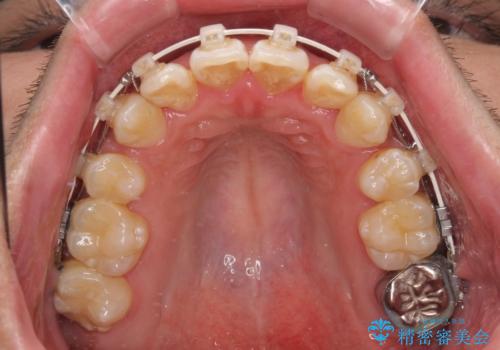

上下左右の小臼歯を抜歯し、歯列を整えるためのスペースを確保

左下は第二小臼歯に根管治療歴があったため、左下のみ第二小臼歯を抜歯しアンカースクリューを併用

それ以外の部位は第一小臼歯を抜歯

矯正中の見た目を気にされていたため、プラスチックブラケット+コーティングワイヤーを使用した、目立ちにくい審美矯正装置を選択しました。